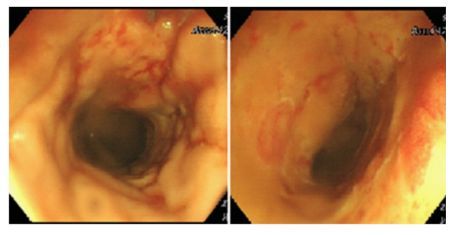

3. Dấu hiệu nội soi và mô bệnh học

Nội soi có nhiều tổn thương từ sung huyết loang lổ, xuất tiết và viêm trợt đến niêm mạc rỉ máu với nhiều vết ăn mòn. Đặc điểm mô học chính của viêm đại tràng do CMV là tăng quá trình apoptosis của tế bào ruột, nguyên nhân là do nhiễm virus, do đó rất khó phân biệt viêm đại tràng do CMV với GVHD (bệnh mảnh ghép – vật chủ) trên sinh thiết đường tiêu hóa. Chẩn đoán xác định ở bệnh nhân ghép thận yêu cầu phát hiện mô học của các thể chứa đặc trưng trên nhuộm haematoxylin và eosin (Hình 3), ngoài các tổn thương đại thể trên nội soi. Hơn nữa, việc phát hiện CMV trong mô cố định bằng formalin bằng hóa miễn dịch, cuối cùng được tích hợp với phản ứng chuỗi polymerase (PCR) của mô nhúng parafin, là một phương pháp có giá trị cao để xác nhận chẩn đoán viêm đại tràng do CMV.